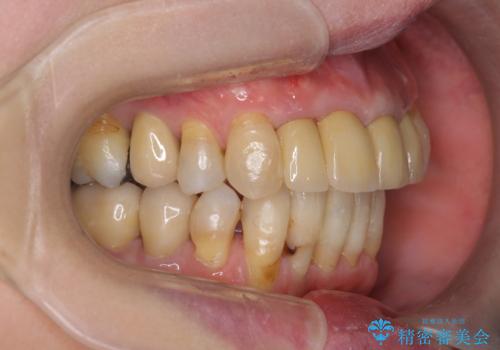

矯正を含む全顎治療

- 前歯の見た目・歯並び・銀歯の見た目の改善を求めて来院されました。

まずガタ付きの強い歯並びをマウスピース矯正インビザラインで整えたのち、セラミック治療による審美性の改善を計画します。

矯正治療が終わったのちに、精度の高いセラミックを装着することでより安定した噛み合わせとなり審美性も兼ね備えた口腔内状態で治療を終了し、今後のメンテナンスを行っていくことができます。